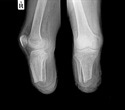

limbs

Limbs. Image Credit: Pixel-Shot/Shuttestock